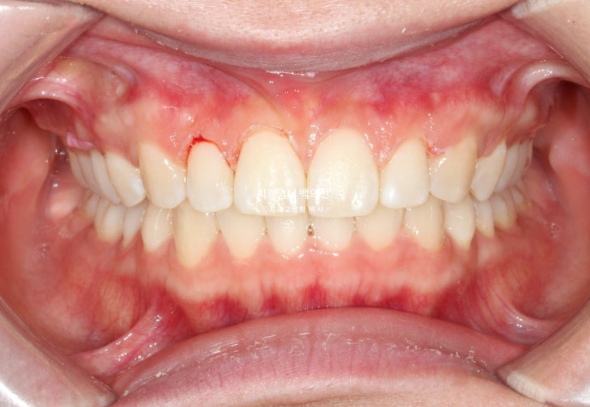

25.02

좋은 교합입니다.

23.04~25.02

유지장치 까지 붙은 모습입니다.